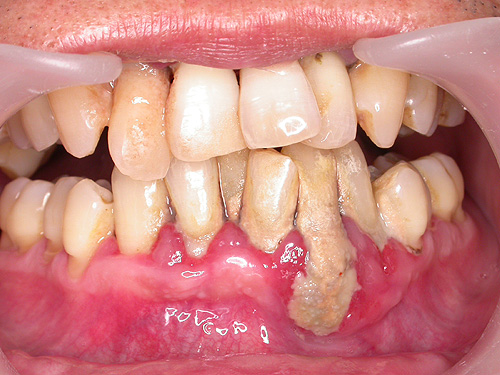

이가 많이 흔들리면 그때는 이미 늦기때문에 심해지기 전에 꼭 치석을 제거하는 스케일링을 하셔야 합니다, 아래 그림은 잇몸을 절개하여 잇몸속에 숨어있는 치석을 나타낸 그림입니다.

그림1같은 경우 치석이 엄청나게 붙어 있으므로 제거를 하고 나면 이뿌리까지 덮고 있던 치석이 없어지므로 처음에는 많이 시릴수 있습니다. 하지만 그 이후 양치질을 잘 하게 되면 건강한 잇몸이 이뿌리를 덮게 되어 건강한 잇몸으로 회복될 수 있답니다. 하지만 그대로 있다면 몇년 안되어 이뿌리까지 녹게 되면 발치할 수 밖에 없답니다. 35세 이후에는 이가 썩어서 빠지는것 보다는 치주병에 의해서 빠지는 것이 더 많답니다. 또한 설명드린것 처럼 스케일링 자체가 치아를 하얗게 만드는 것은 아니랍니다. 물론 치석이 붙어 있는 부분은 깨끗하게 되겠죠. 그림1같은 경우.. ^.^